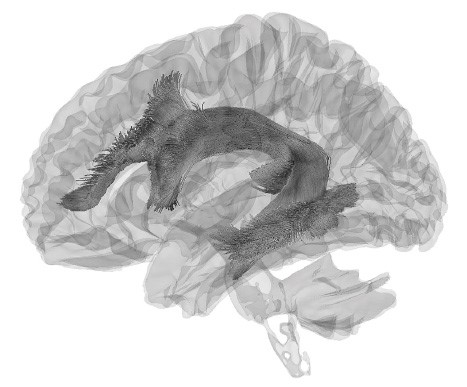

Аркуатный пучок

Как же взаимодействуют зоны Брока и Вернике? Это происходит при помощи аркуатного, или дугообразного, пучка – группы нервных волокон, по которым информация от слуховой коры поступает к моторной и обратно (рис. 4). Впервые этот путь коммуникации между речевыми центрами мозга описал американский невролог Норман Гешвинд, живший в середине ХХ века.

Рис. 4. Схематичное изображение зоны Брока, зоны Вернике и соединяющего их аркуатного пучка

Если аркуатный пучок повредить, то у человека появятся проблемы: сохраняя способность понимать устную и письменную речь, он не сможет повторить слова, которые услышал или прочитал. Такой пациент будет говорить с ошибками, и, осознавая это, самостоятельно исправить их он не сможет.

Рис. 5. 3D-модель аркуатного пучка, соединяющего зоны Брока и Вернике. Метод, при помощи которого сделано изображение, называется диффузионно-тензорной трактографией (разновидность МРТ). Снимок стал финалистом конкурса научной фотографии Wellcome Image Award в 2017 году.

Источники: Stephanie J Forkel and Ahmad Beyh, Natbrainlab, King's College London; Alfonso de Lara Rubio, King's College London